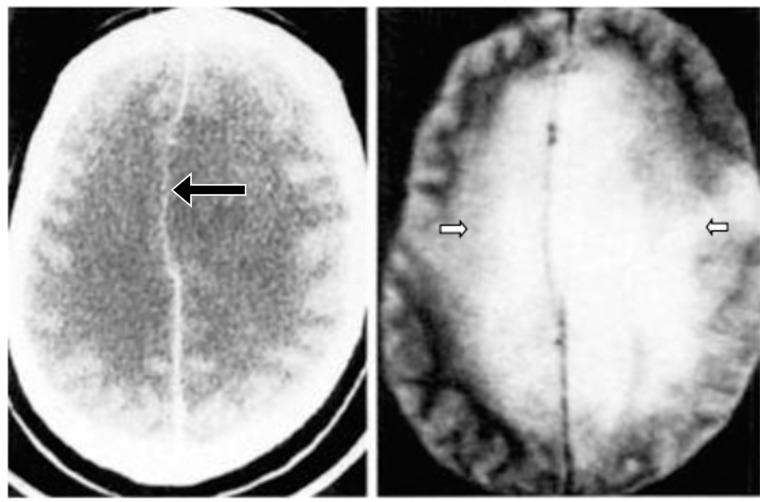

Ultra-high contrast (UHC) MRI describes forms of MRI in which little or no contrast is seen on conventional MRI images but very high contrast is seen with UHC techniques. One of these techniques uses the divided subtracted inversion recovery (dSIR) sequence, which, in modelling studies, can produce ten times the contrast of conventional inversion recovery (IR) sequences. When used in cases of mild traumatic brain injury (mTBI), the dSIR sequence frequently shows extensive abnormalities in white matter that appears normal when imaged with conventional T-fluid-attenuated IR (T-FLAIR) sequences. The changes are bilateral and symmetrical in white matter of the cerebral and cerebellar hemispheres. They partially spare the anterior and posterior central corpus callosum and peripheral white matter of the cerebral hemispheres and are described as the whiteout sign. In addition to mTBI, the whiteout sign has also been seen in methamphetamine use disorder and Grinker's myelinopathy (delayed post-hypoxic leukoencephalopathy) in the absence of abnormalities on T-FLAIR images, and is a central component of post-insult leukoencephalopathy syndromes. This paper describes the concept of ultra-high contrast MRI, the whiteout sign, the theory underlying the use of dSIR sequences and post-insult leukoencephalopathy syndromes.

超高对比(UHC)MRI 描述了这样一些 MRI 形式,在常规 MRI 图像上几乎没有或没有对比,但在 UHC 技术中可以看到非常高的对比。其中一种技术使用分裂相减反转恢复(dSIR)序列,在建模研究中,该序列可以产生比常规反转恢复(IR)序列高十倍的对比度。当用于轻度创伤性脑损伤(mTBI)时,dSIR 序列经常在白质中显示出广泛的异常,而在使用常规 T 液衰减反转恢复(T-FLAIR)序列成像时,白质看起来正常。这些变化在大脑和小脑半球的白质中是双侧对称的。它们部分保留了前中央和后中央胼胝体以及大脑半球的外周白质,被描述为“白化征”。除了 mTBI 之外,在没有 T-FLAIR 图像异常的情况下,该白化征也出现在苯丙胺使用障碍和 Grinker 髓鞘病(缺氧后迟发性白质脑病)中,是创伤后白质脑病综合征的一个核心组成部分。本文描述了超高对比 MRI、白化征、dSIR 序列使用的理论以及创伤后白质脑病综合征的概念。